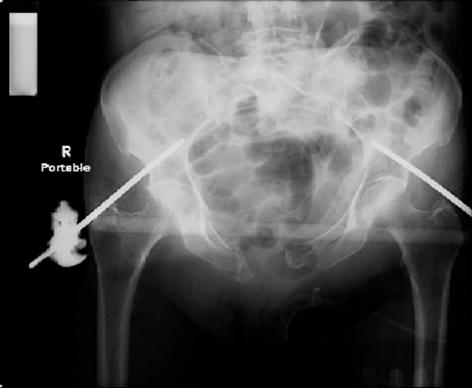

pt treated that night with I/D and supra-acetabular frame to close the ring. consideration was given for SI screws bilateraly, but given time of night and other factors decision made not to proceed.

so the question is what next operatively if anything? concerns are infection, nonunion anteriorly and possible incompetence of the pelvic floor which may lead to prolapse issues. right rami are comminuted and plating may entail ilioinguinal approach to extend plate laterally to right iliac wing. retrograde screw up right rami is an option but I am not convinced it will add much. adding SI screws very doable, but major concern is restoring anterior ring. so far wound is clean and closed over a drain, and I have no plans to open it back up and wash again.

any thoughts? would anyone plate the pubic symphysis to close the gap and leave the more lateral rami fractures alone? the most recent pelvic case on this website involved pts with suprapubic catheters and antibiotic options including resorbable beads. I wonder how many people would plate and place antibiotic beads. thanks.

attached are several CT cuts. please let me know if you need more. the CT is pre-pelvic ex-fix placement.